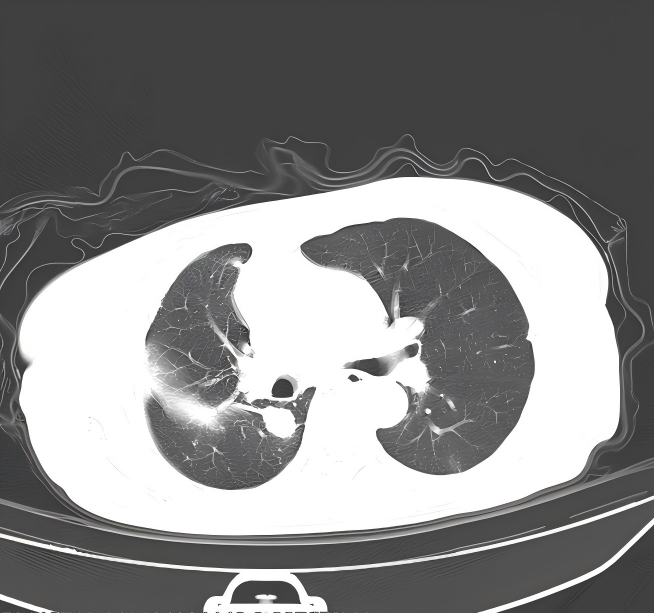

胸部+上腹部增强CT:2023.12.04我院门诊肺部CT示:1.左肺上叶结片影;右肺上叶及右肺门结块,右肺门形态增大,右肺下叶部分支气管截断,多考虑肿瘤性病变,请结合临床病史及对比前片。2.右侧胸腔积液;伴右下肺膨胀不全。3.扫及肝脏囊性灶;胆囊结石。

胸水脱落细胞学结果:

2.png

1、胸水引流和灌注化疗:于2023.12.04 行右侧胸腔积液穿刺引流术,引流出约1500m1淡红色胸水,送检细胞学可找到肿瘤细胞。于12.08 、12.15行2次顺铂(40mg)胸腔灌注化疗,过程顺利,未诉不适。复查胸部CT提示胸水消失。

OoCNxjw6Pe2NhnUiFbeWjYFJJF3cHziA.png

CT.jpg1.png2.png3.png